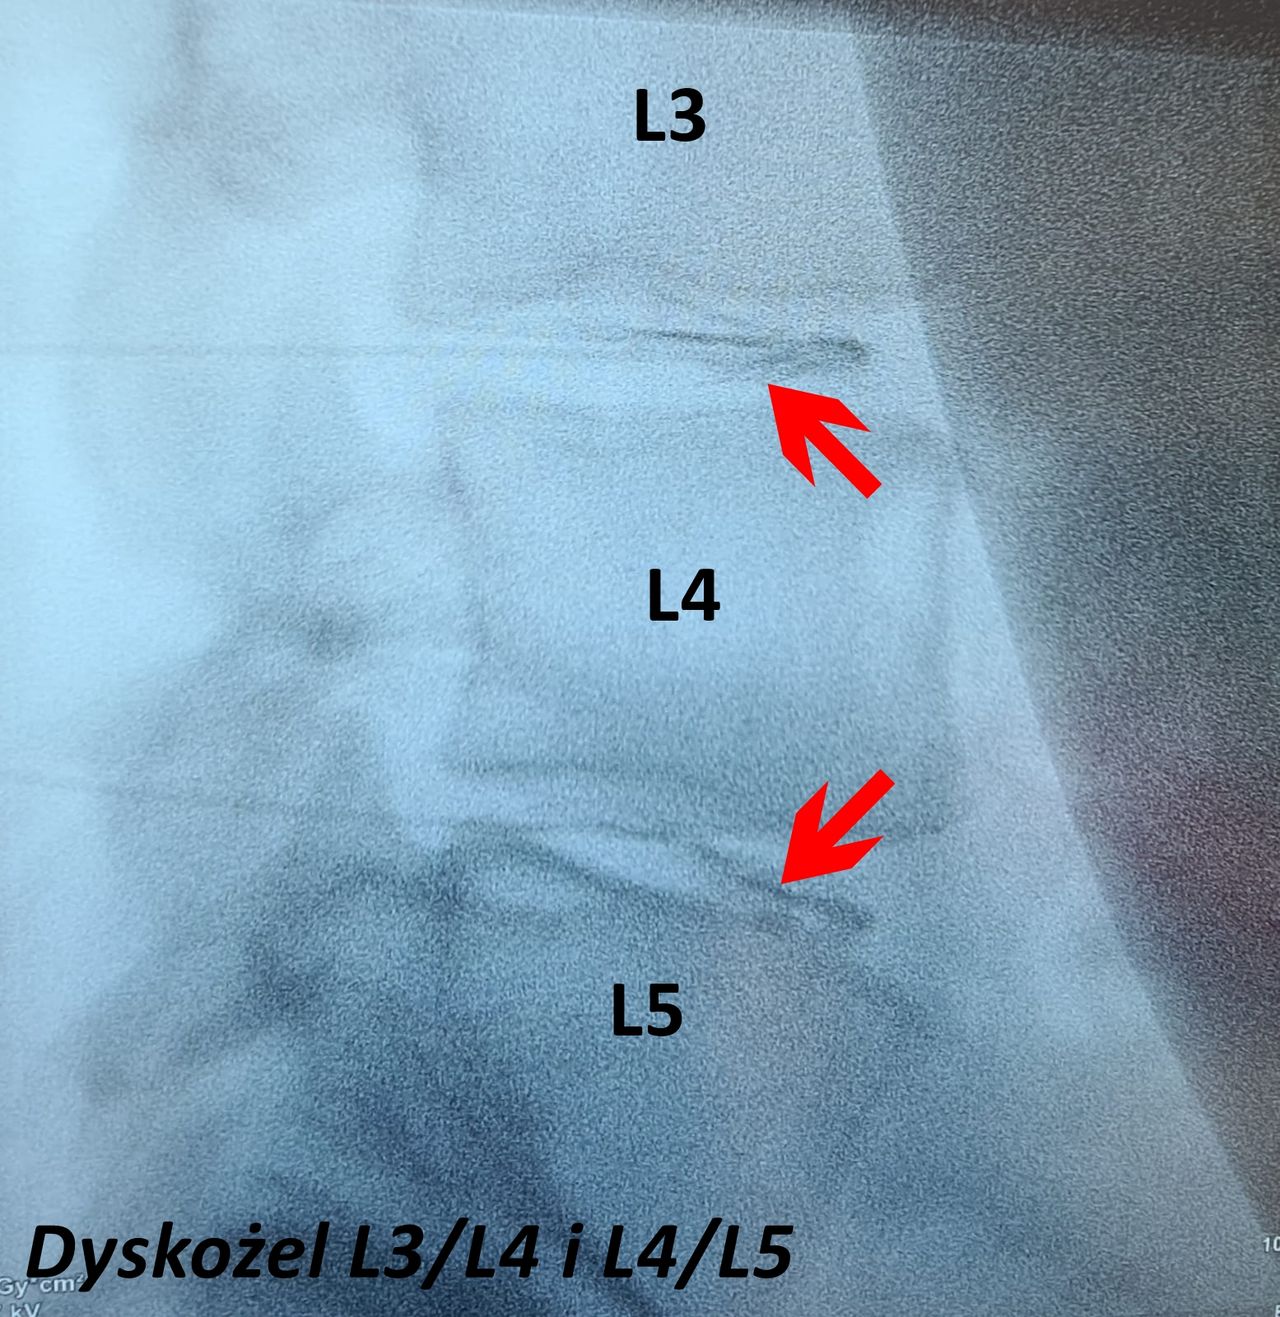

- zabiegi dyskożelu (Discogel) i nukleoplastyki kręgosłupa szyjnego, piersiowego i lędźwiowego, kwas hialuronowy, komórki macierzyste, termolezja, kriolezja